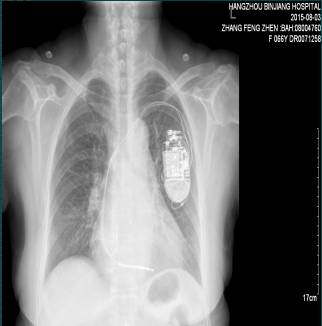

1.女性,66岁,杭州本地居民.于2015.08.03入院。

2.反复晕厥7年,ICD植入后5月,再发晕厥后5天。

3.患者7年来反复出现晕厥,5月前症状再发,每次持续时间数十秒至数分钟,结合心电图、心超、冠脉造影结果,诊断“扩张性心肌病”心电图提示非持续性室速,接受双腔ICD植入术;5天前,患者类似晕厥症状再发,发作前驱有心悸和胸部不适感,无发热,无头痛,无四肢抽搐;

⑥室性心动过速,ICD植入术后;